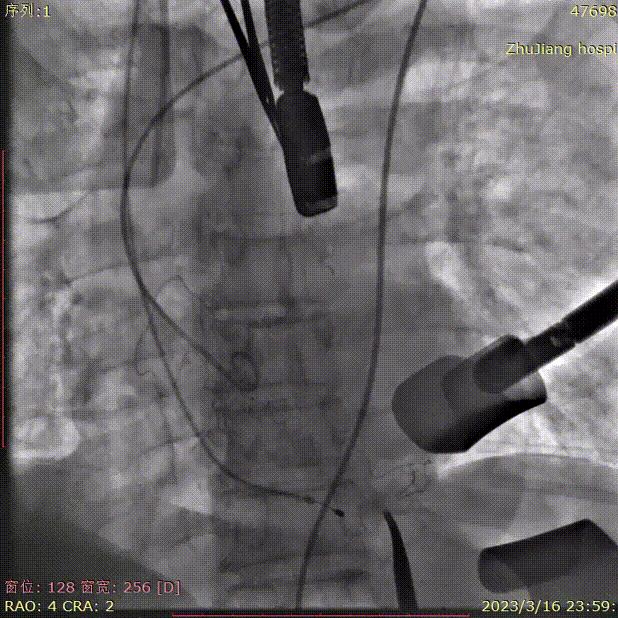

术中造影角度RAO 4°,CRA 2°(其它参考角度如下图):

猪尾放置于无冠窦行根部造影,可见瓣叶钙化影及明显造影剂反流: